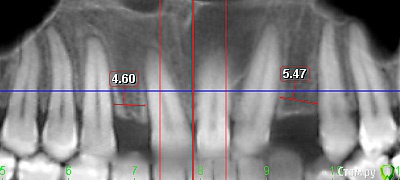

Игорь Пеликан Опубликовано 14 ноября, 2018 Поделиться Опубликовано 14 ноября, 2018 Тут ортодонию нужно доделать,нижний центр гуляет,нет нормальной оклюзии в боковой группе,в 23 редукция толщины корня субгингивально(под размеры двойки),и зениты 12,22 выровняются.Около импланта в позиции 23 зенит поднять симметрично к 13,чуть расширить трема должна уйти,можно ещё мезиально вытянуть,и за счёт 24 закрыть её. 1 Ссылка на комментарий

Romanson Опубликовано 15 ноября, 2018 Автор Поделиться Опубликовано 15 ноября, 2018 (изменено) Тут ортодонию нужно доделать,нижний центр гуляет,нет нормальной оклюзии в боковой группе,в 23 редукция толщины корня субгингивально(под размеры двойки),и зениты 12,22 выровняются.Около импланта в позиции 23 зенит поднять симметрично к 13,чуть расширить трема должна уйти,можно ещё мезиально вытянуть,и за счёт 24 закрыть её.Это сложная ортодонтическая ситуация?Как поняли, что низ гуляет? Изменено 15 ноября, 2018 пользователем Romanson Ссылка на комментарий

Игорь Пеликан Опубликовано 17 ноября, 2018 Поделиться Опубликовано 17 ноября, 2018 Это сложная ортодонтическая ситуация?Как поняли, что низ гуляет?Учитывая возраст,наверняка стертость жевательных поверхностей боковой группы зубов,состояние ВНЧС,адаптацию мышечного апарата под определенную технику пережёвывания пищевого комка этот клинический случай, возможно, не может быть излечен в полном объёме,только за счёт ортодонтии.Предположил на основании последнего фото Ссылка на комментарий